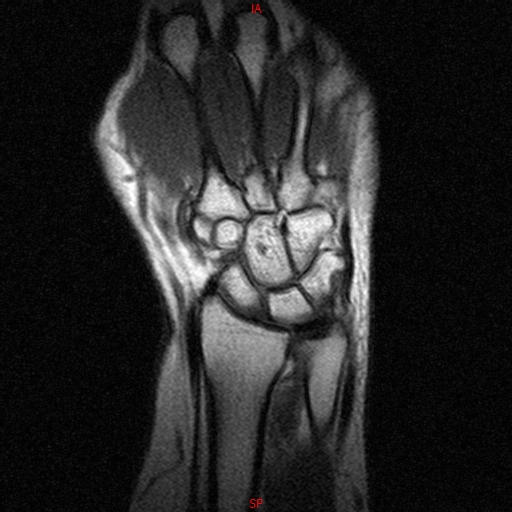

• Resonancia PATOLÓGICA DE MUÑECA - FRACTURA ESCAFOIDES

• Resonancia NORMAL MUÑECA COR T1

• Resonancia NORMAL MUÑECA COR T1 3D FATSAT